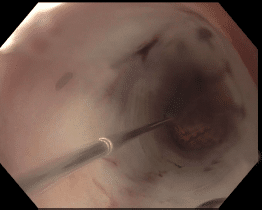

A 76-year-old gentleman with progressive solid food dysphagia and a long history of tobacco use was found to have a malignant appearing, partially obstructing mass spanning 1-2cm of the mid esophagus (Fig 1A) with biopsies demonstrating poorly differentiated adenocarcinoma. Subsequent imaging revealed liver metastases confirming Stage IV disease. Oncology referred the patient for indefinite palliative esophageal stent placement to allow improved oral nutrition and quality of life while undergoing chemotherapy.